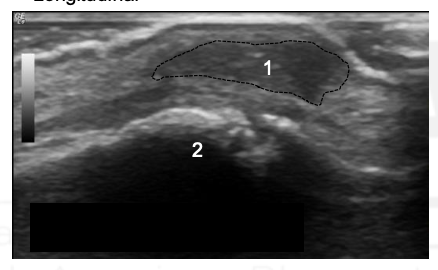

What are 1 and 2?

1 - Middle phalanx

Ganglionic Cyst

What is the arrow pointing to?

How do you differentiate Ganglions, Neurofibromas/Schwannomas, and Giant Cell Tumors?

Ganglions - Anechoic + posterior acoustic enhancement + stalk from synovial cavity or tendon sheath; if nodular or doppler signal inside = cancer

Neurofibromas/Schwannomas - nerve tail + posterior acoustic enhancement

Giant Cell Tumors - Hypoechoic - posterior acoustic enhancement

What is posterior acoustic enhancement?

The region deep to a fluid collection will be relatively hypoechic as more sound waves are able to reach that tissue than the tissue to either side.